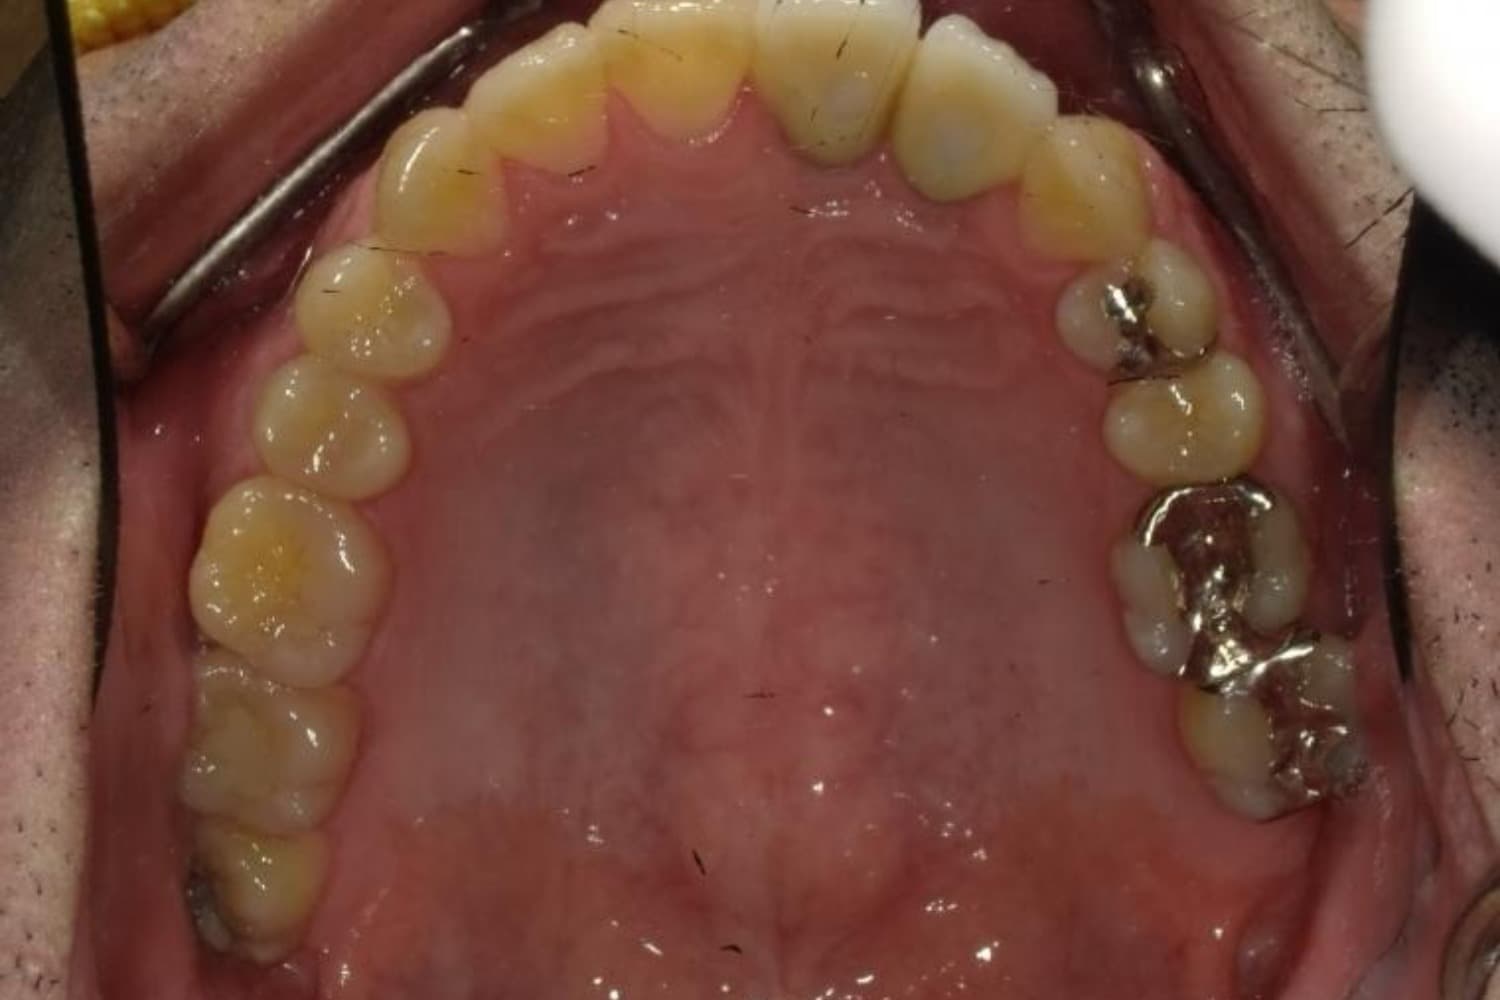

下顎大臼歯3本欠損症例

Before

After

左下第一大臼歯は保存が困難な状態であったため抜歯をおこないました。あわせて、ご来院時から欠損していた右下第一・第二大臼歯も含め、欠損部の補綴方法についてご説明し、インプラント治療を選択されました。

年齢

60歳

性別

男性

主訴

左下の第一大臼歯は別の医院で治療中でしたが、治療が思うように進まず、加えて他の箇所にも痛みが続いたことから、当院にご相談いただきました。

治療期間

10ヵ月

費用

140万円

副作用・リスク

インプラント治療は外科的な処置を伴い、多少の腫れや痛みが出ることがあります。 多くの場合は鎮痛薬で和らげることができます。